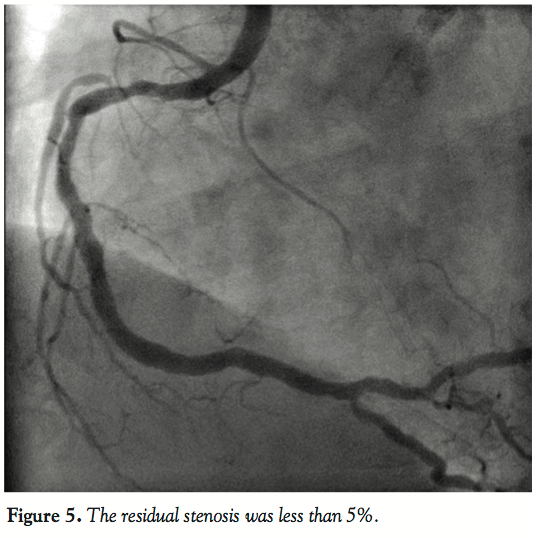

In an effort to insert the intravascular ultrasound catheter up to the mid portion of the RCA, we engaged the RCA more deeply using the DIO thrombus aspiration catheter to gain back-up force. Stenting was accomplished with a 3.0 mm × 23 mm Cypher select plus stent (Cordis, Johnson and Johnson Interventional System) delivered at 14 atm. The residual stenosis was less than 5%. This excellent result was accomplished by deep engagement using a DIO thrombus aspiration catheter.